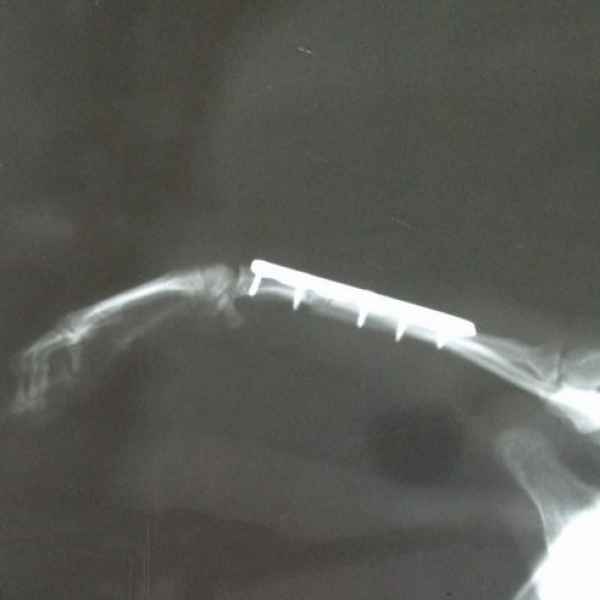

Вот что значит неудачно спрыгнуть с дивана. Это рентгеновские снимки одного из наших пациентов. Сначала хозяева обратили внимание на хромоту, а потом поняли, что у питомца очень болит лапа. Ещё бы не болело - поперечный перелом костей предплечья. Операция, установка DCP-пластины, восстановление, и он снова активный и жизнерадостный.

Этот пациент поступил к нам с кусаной раной левой грудной конечности После рентгенологического исследования обнаружили перелом костей предплечья. Сложность операции заключалось в том, что дистальный отросток лучевой кости был очень коротким. Хирургом нашей клиники было принято решение установить блокируемую lcp пластину. В данный момент пациент полностью восстановился..